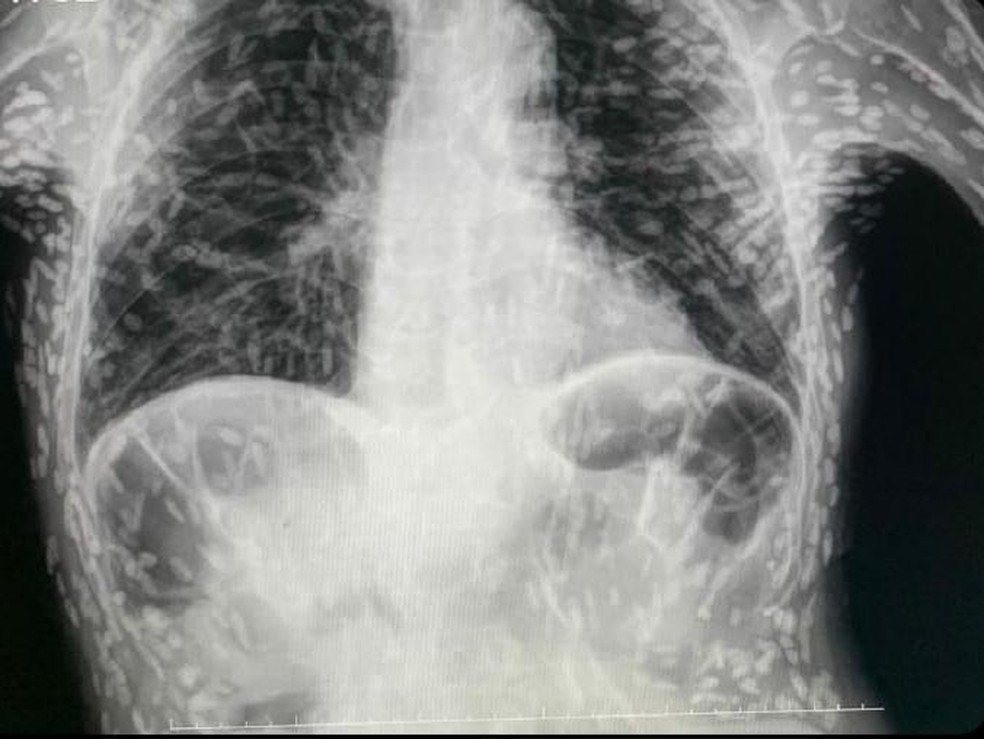

Em abril do ano passado,um caso de exame semelhante viralizou também no Brasil. Um paciente não identificado teve seu exame revelado nas redes sociais pelo Hospital das Clínicas de Botucatu,em SP. O paciente apresentava tosse constante há dois meses quando o exame foi solicitado. Os ovos de tênia encontrados no tórax já estavam mortos e calcificados,ou seja,não apresentavam risco a ele.

Os ovos de tênia encontrados no tórax já estavam mortos e calcificados,já não apresentavam riscos — Foto: Reprodução/ Twitter